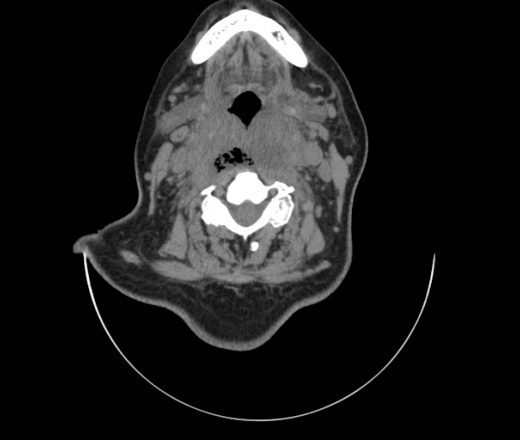

Женщина поступила в х/о спустя 4 дня после того как при употреблении карася подавилась костью.

Наличие газа в средостении на протяжении тел С2-С6 (медиастинальна эмфизема); рыбная кость на уровне тела С6.

При всем уважении, но говорить о медиастинальной эмфиземе, оценивая мягкие ткани шеи, как-то слишком резко. На мой взгляд, это ретрофарингеальное пространство.

Согласен с Вами; конечно, наличие газа в клетчатке ретрофарингеального пространства (затмение с опечаткой..). К сожалению, процесс "продвигается" к медиастиниту. Но почему никто, не отмечает наличие рыб. кости; или это для Всех очевидно?

Кость то мы сразу выявили, размеры где то 17*2мм, но ее так и не получается найти в этой каше